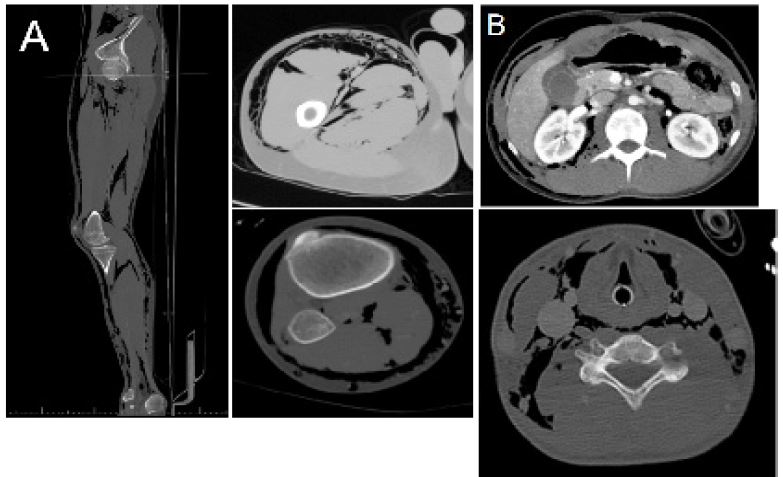

Our case involves a 17-year-old incarcerated male who presented to the ED 8 hours after stabbing his right posterior calf with a “glitter pen.” His only past medical condition was a well-controlled seizure disorder. Upon presentation, he was febrile (39.5 C), moderately tachycardic, hypotensive (90/50), ill appearing, with complaints of chest pain and shortness of breath. Physical exam revealed an approximately 1cm right calf puncture wound, calf tenderness, faint but non-spreading erythema in the area of the wound, and marked crepitus of the proximal right leg, abdomen, bilateral flanks, chest wall, and neck. Imaging revealed significant subcutaneous air involving these sites (Figure 1). White cell count, lactic acid, and CRP were all within normal limits. Broad spectrum antibiotics and aggressive volume resuscitation were initiated, and he was taken to the OR emergently out of concern for necrotizing soft tissue infection. In the OR, there was extensive gas within the muscles, but no purulent fluid, necrosis, or foul odor were present in three distinct sites explored.

Post-operative CT imaging demonstrated marked subcutaneous gas as well as a new moderate volume abdominal free fluid (Figure 1). On exam, the patient had a new complaint of abdominal tenderness. Considering this new finding in addition to free fluid, the patient was taken for exploratory laparotomy given the possibility of a retroperitoneal source of the subcutaneous gas. There was extensive retroperitoneal and omental emphysema without evidence of infection or necrosis. There was an additional finding of a moderate amount of simple-appearing as cites. After the operation, the patient spent 1 day in the ICU. Antibiotics were discontinued due to negative blood and wound cultures. He remained stable and without sign of infection and was discharged 3 days later.

Figure 1: CT imaging of demonstrating subcutaneous emphysema. (A) CT of the right lower extremity, which, combined with the patient’s vitals were concerning for necrotizing fasciitis; however, exploration revealed no evidence of infection. (B) After the initial exploration, repeat imaging demonstrated new moderate-volume free fluid accompanied with new-onset abdominal tenderness, warranting a return to the operating room for exploratory laparotomy.